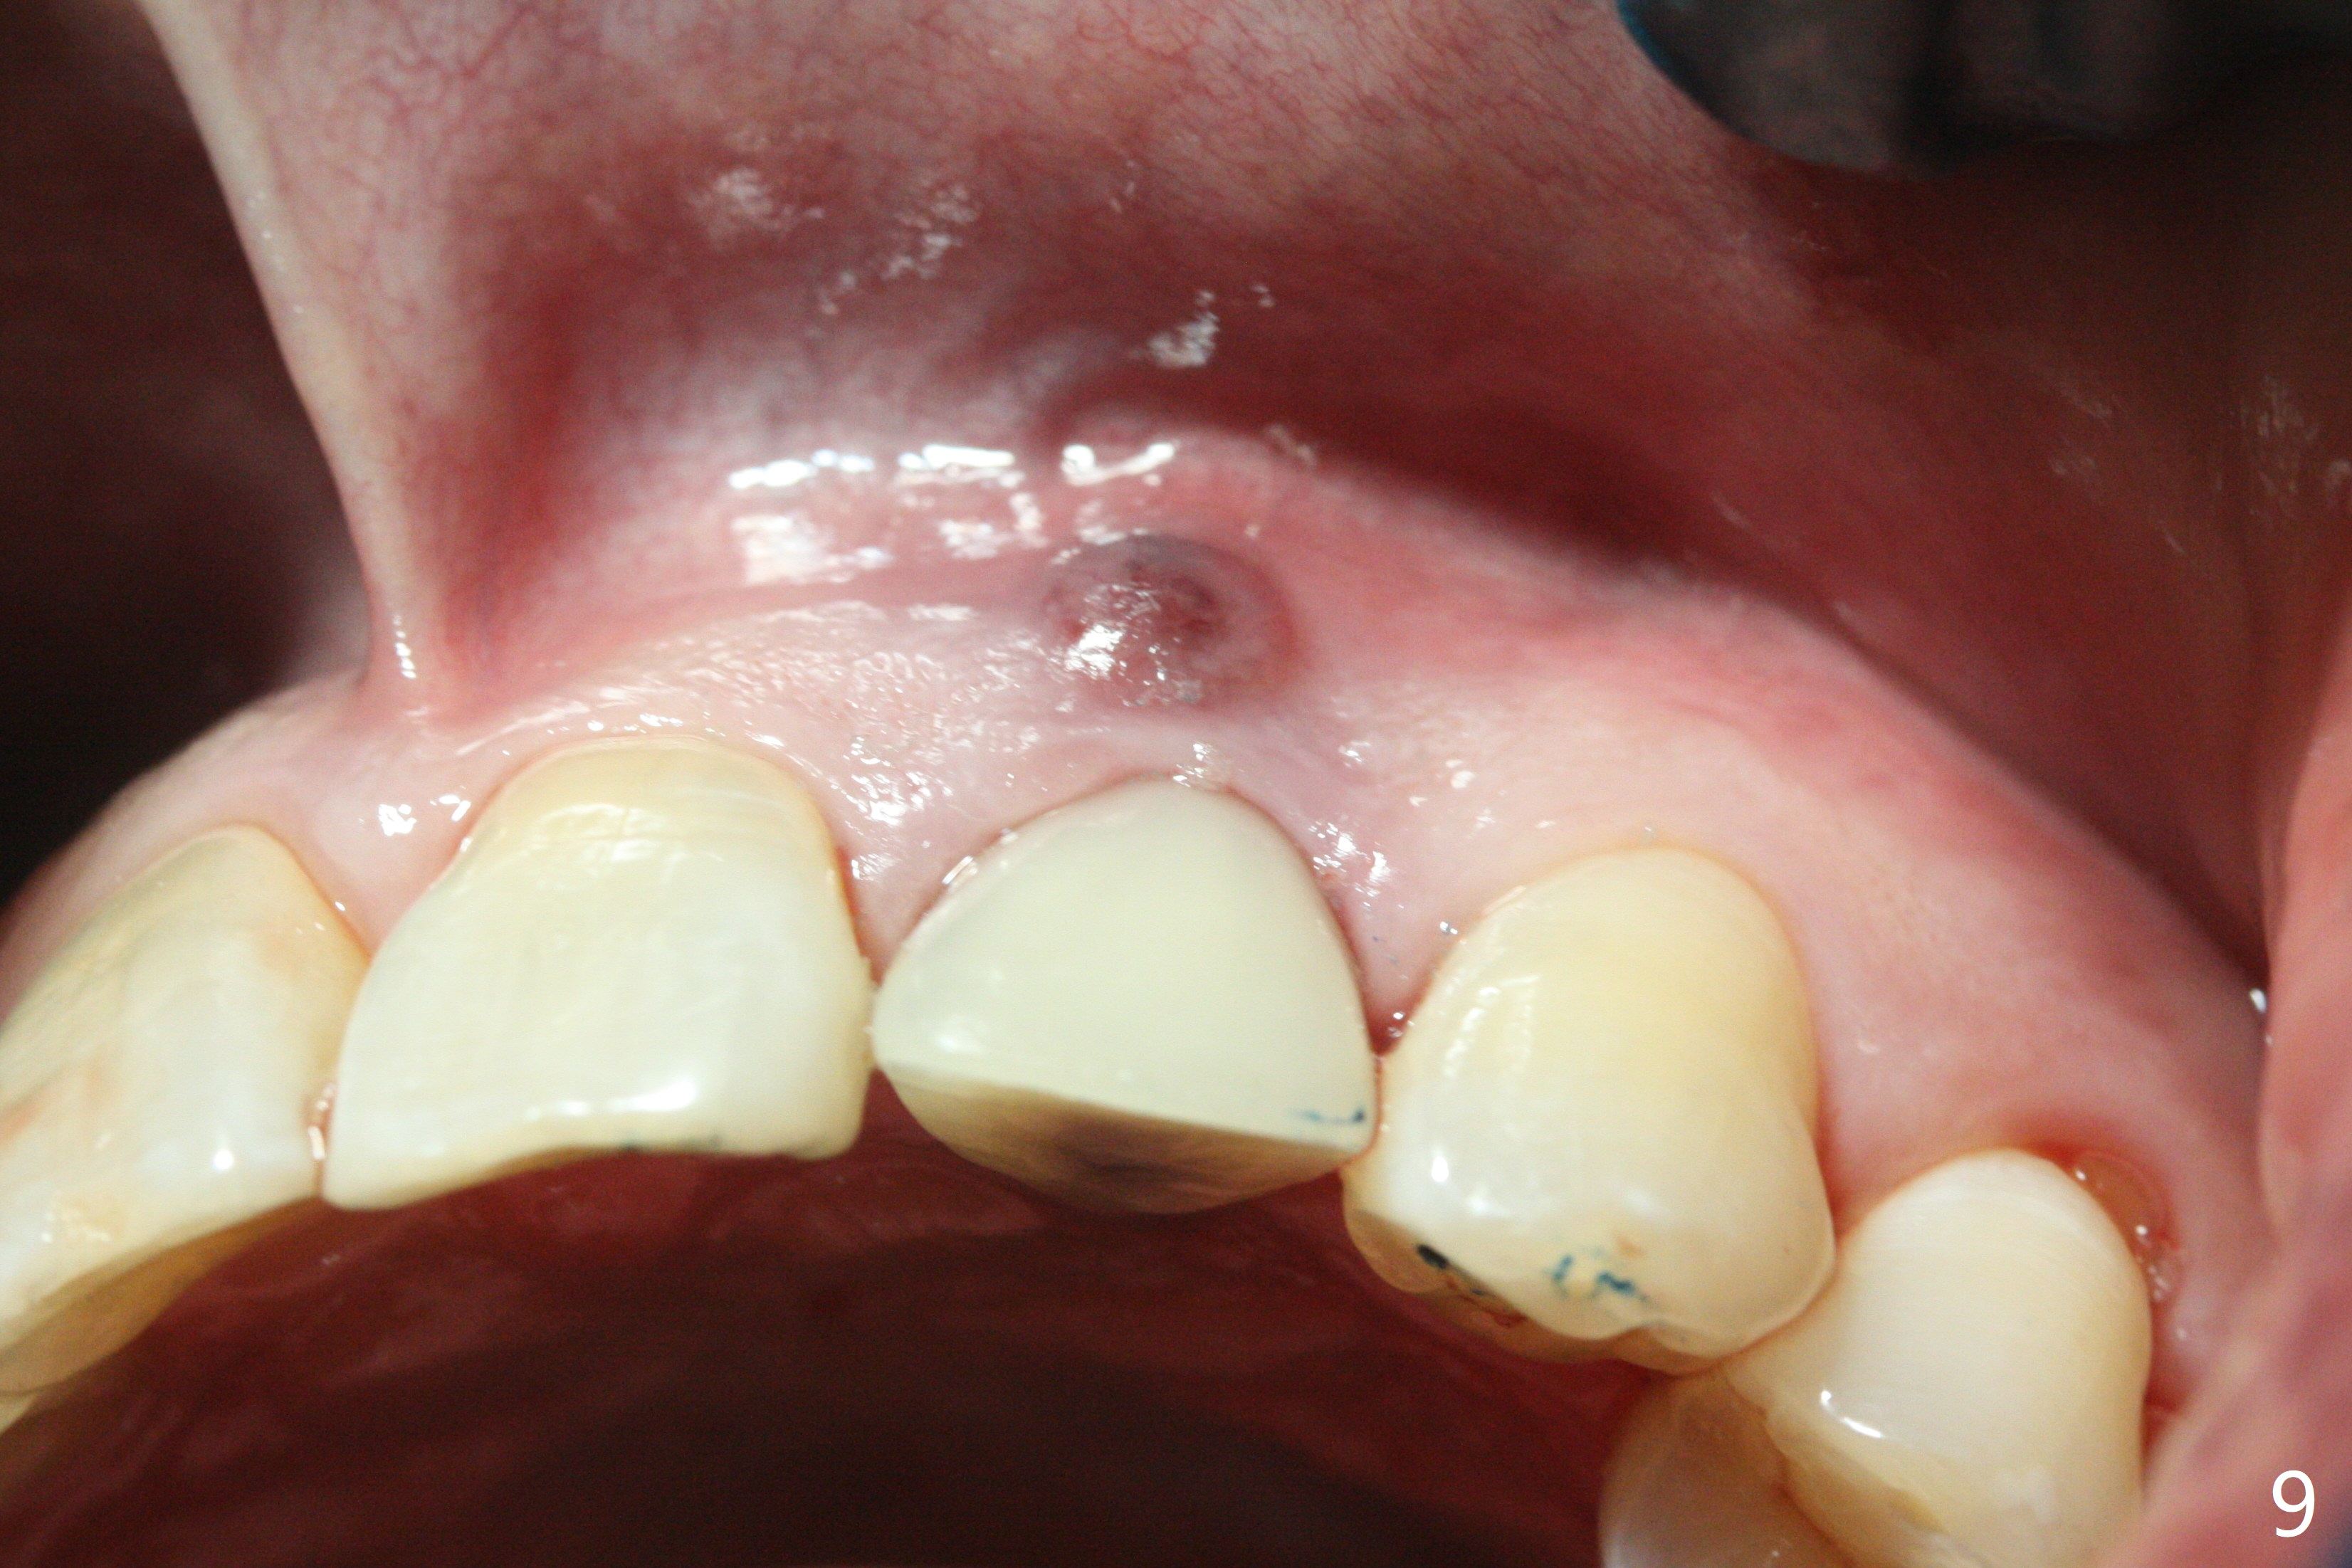

病人回来带来瘘道(图一),不过不会增加难度,病牙去除,它便自动消失。尽管颊侧骨壁完全失去,颊侧牙龈仍丰满(图二),为什么呢?第一,因为粗大牙根存在,第二两旁牙齿,牙槽骨撑着帐篷(侧切牙颊侧牙龈),第三,牙冠。为了防止术后牙龈塌陷,尽量不切开,即刻放置植体(牙根);由于前牙缘故,这次植体不能很大,所以植骨必须过度(over grafting),最后即刻制作临时牙冠,撑住牙龈。这就是所谓每个人进入角色。这个牙根有一种先天性畸形:dens in dent (图三(腭侧观):箭头)。尽管腭侧牙根畸形,腭侧骨壁吸收临床上并不严重,所以钻洞仍偏腭侧。当预定最后钻头还在钻洞时,填入大量粘性骨块(图四:*),细长植体还没有完全卡入鼻底(图五),最后好像可以(图六,七)。植体,骨粉入位(图八),最后临时牙冠出场(图九)。尽管植体小,术后一周临时牙冠仍然可以维持牙龈原有形状(emergency profile,图十:箭头(*:树脂强化牙冠固定))。图十一以不同角度显示瘘道缩小。术后三周取出有些松动的临时牙冠,骨粉虽然还没有被肉芽组织整合,但是显得正常,周围牙龈健康(图十二)。术后4个月牙龈形态正常(图十三),没有触痛;颊侧骨板轻度凹陷(图十四);骨粉仍在原位(图十五)。术后7个月骨粉仍在原位(图十五,十六,但是冠部密度减低(可能骨粉流失,需要牙周或者树脂敷料保护)),没有螺纹暴露。但是牙冠边缘暴露,说明牙龈收缩(图十七,与图十三对比),颊侧骨板仍塌陷(图十八)。插入龈线取得多个目的:修整基台边缘,取模,颊侧牙龈推向颊侧,有利于即将衬里牙冠龈缘进入龈下(图十九)。取模后牙冠边缘(图二十:<)衬里,然后修整,变窄,以便插入龈下,促进颊侧牙龈下降(图二十一,二十二)。术后8个月牙冠粘固前牙龈健康(图二十七,八),牙冠(图二十九)固位后,病人满意(图三十),咬合调整(图三十一),注意腭侧粘固粉流出通道(<)。